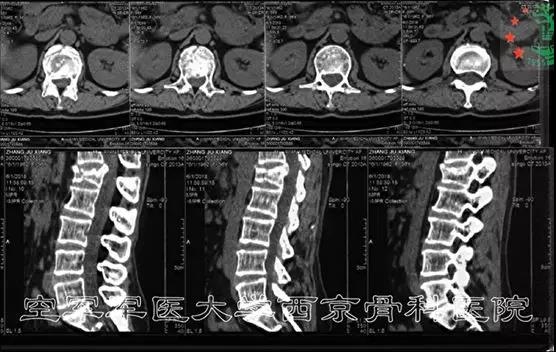

术前CT